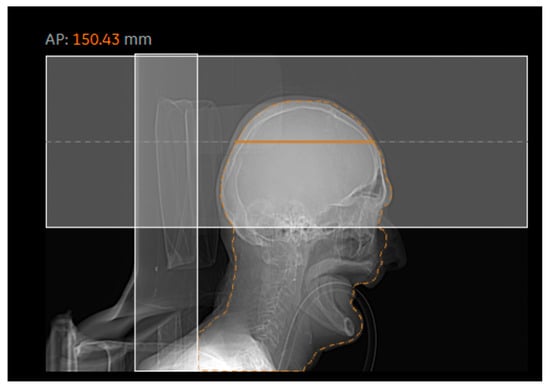

Figure 3 and Figure 4 generally show an excellent correlation in the SSDE comparison, except for the skull region. We found that the discrepancy between the two programs could be related to the incorrect determination of the central slice by the DWTM program. Per Juszczyk et al. [24], DWTM malfunction for detecting the central slice could be related to the tilted gantry at the central slice at a different location compared to the actual central slice of the DWTM (Figure 9).

Figure 9. Representative image showing an inadequately defined central slice by DWTM.